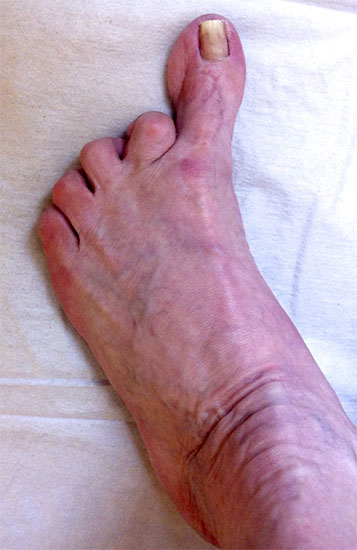

Klinisches Erscheinungsbild eines Hallux varus (eigenes Bildmaterial)

Abbildung 1